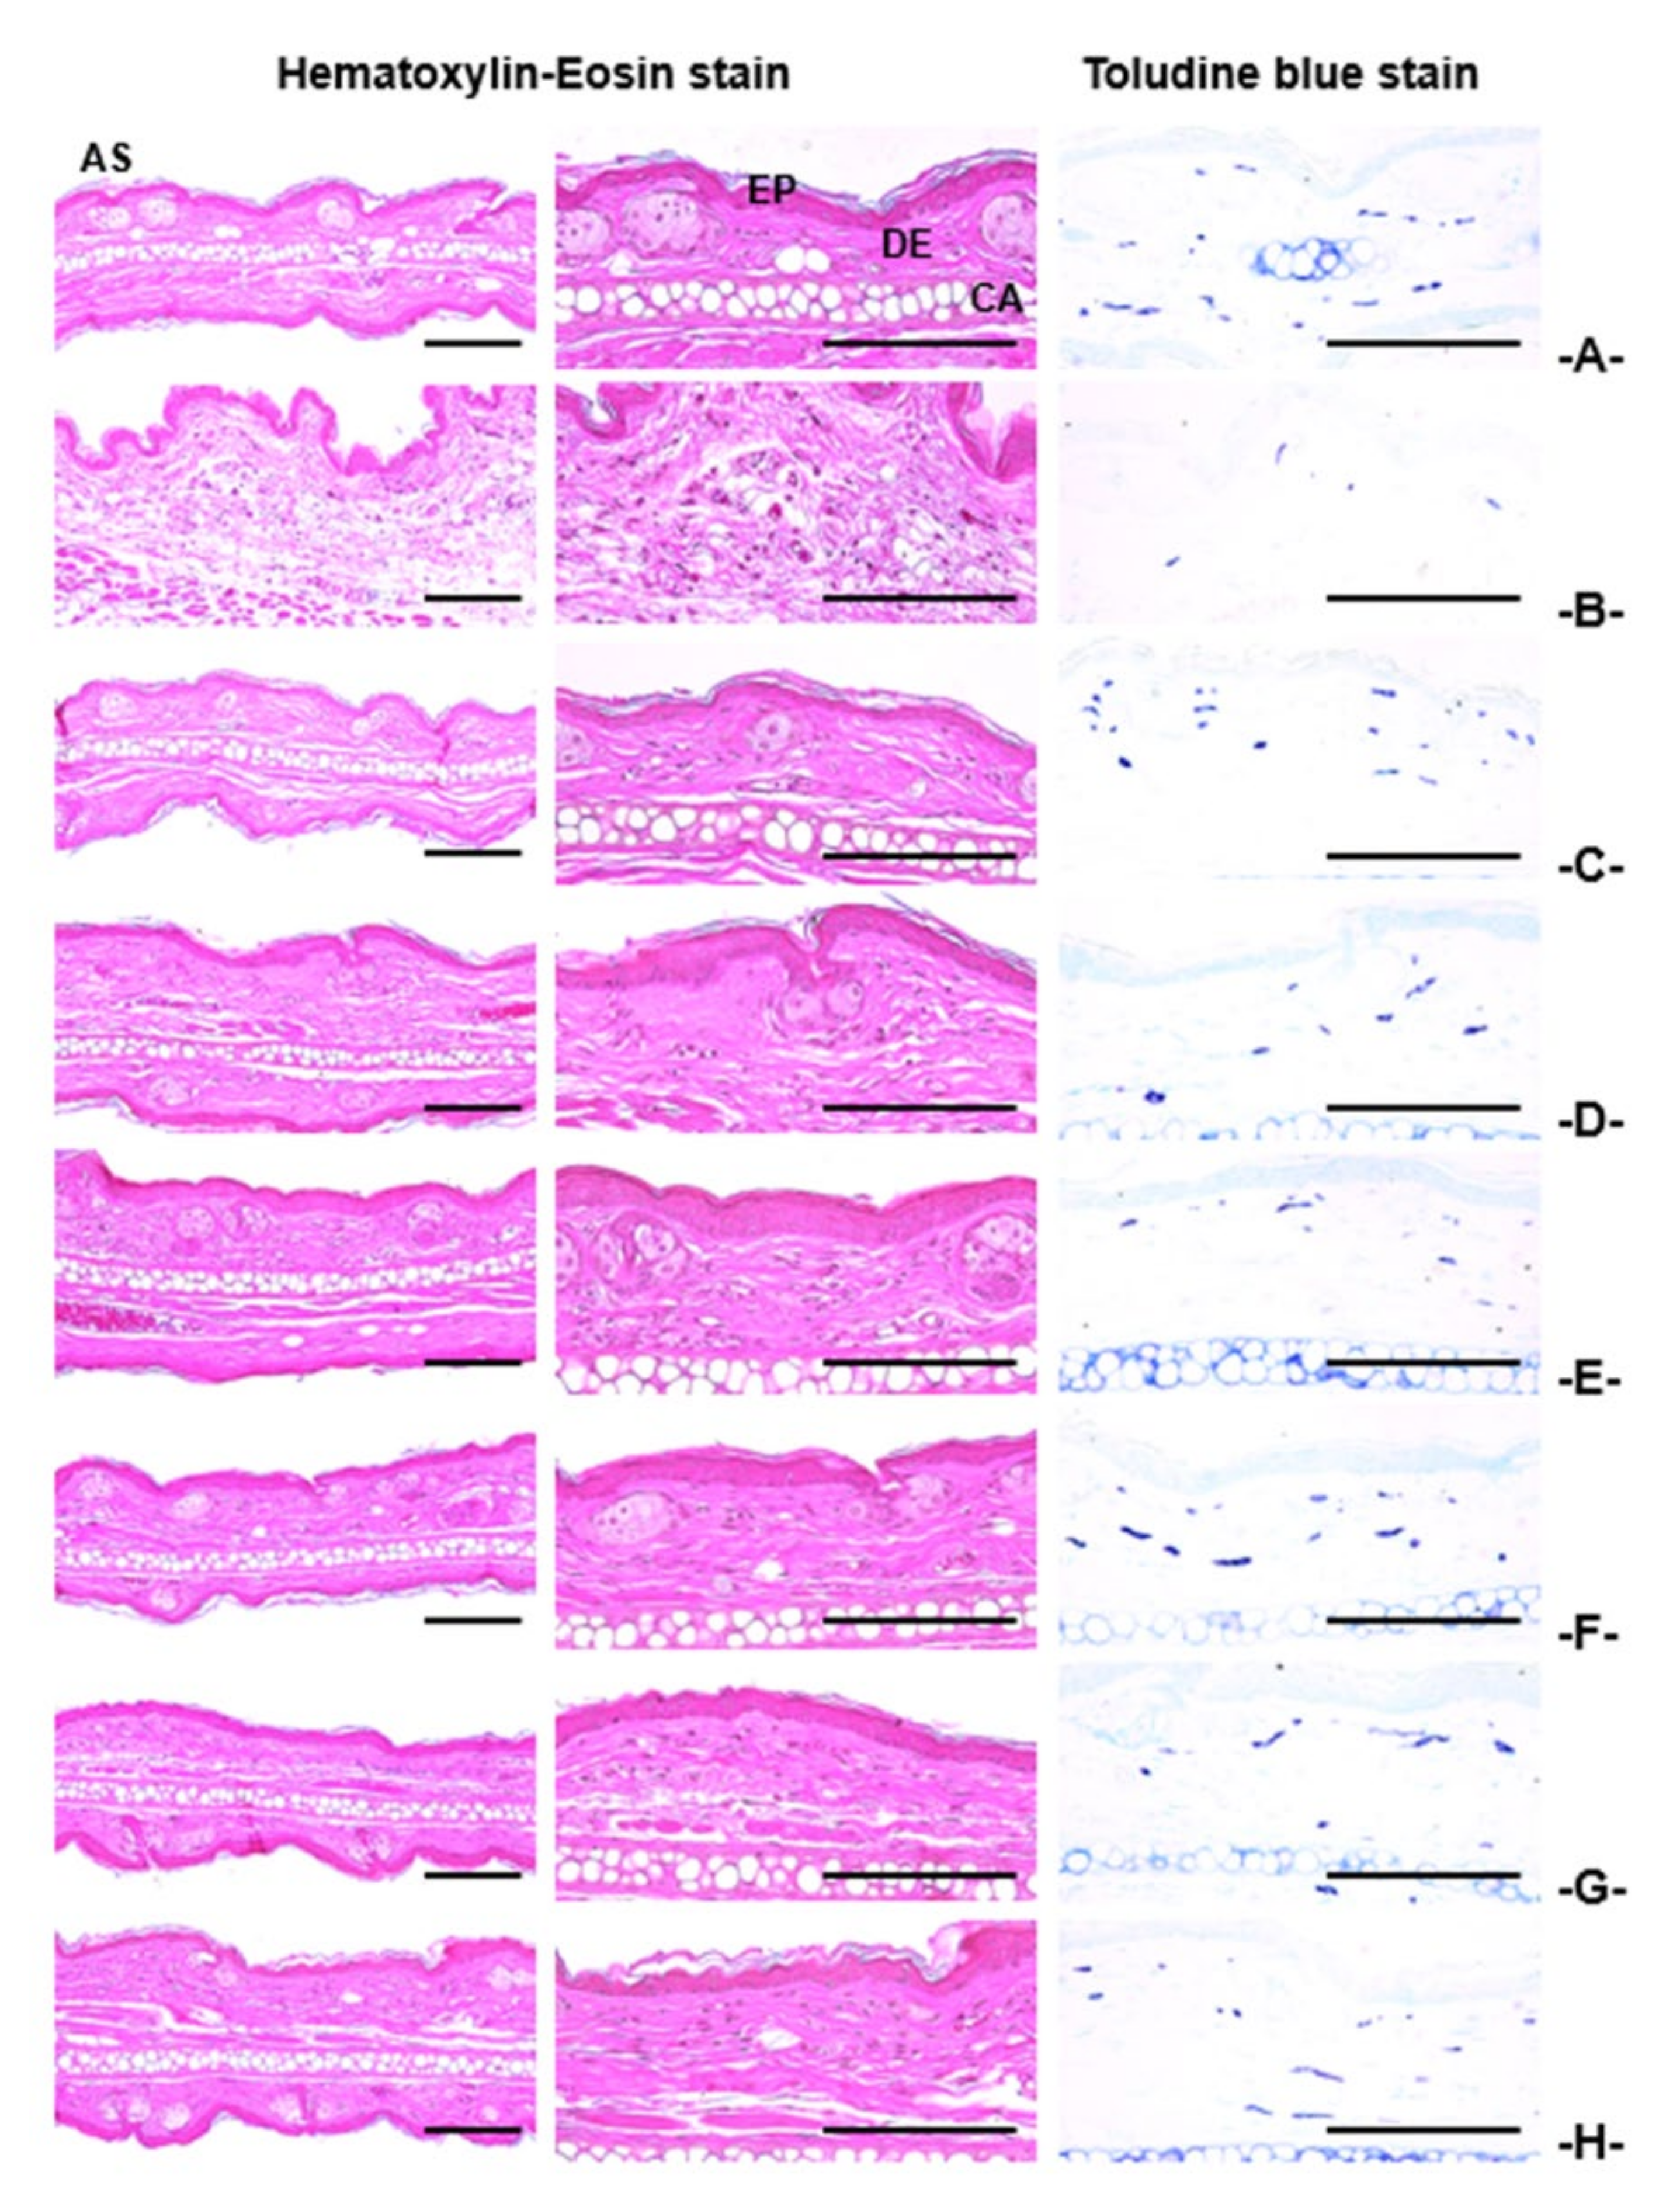

3.4.4. Histopathological Findings on the Ear